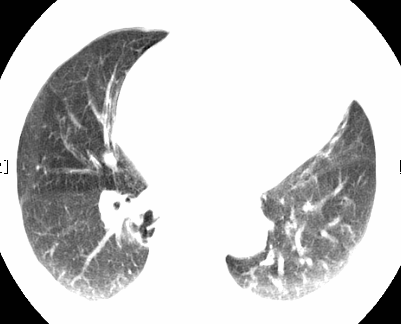

标题: CT26680:肺部右下肺静脉干结节的界定 [打印本页]

标题: CT26680:肺部右下肺静脉干结节的界定

经追查说有支扩咯血病史,但不确定

考虑1、周围型肺癌,2肺静脉畸形,前者可能大,建议增强检查。

不排除右肺下叶周围型肺癌可能。